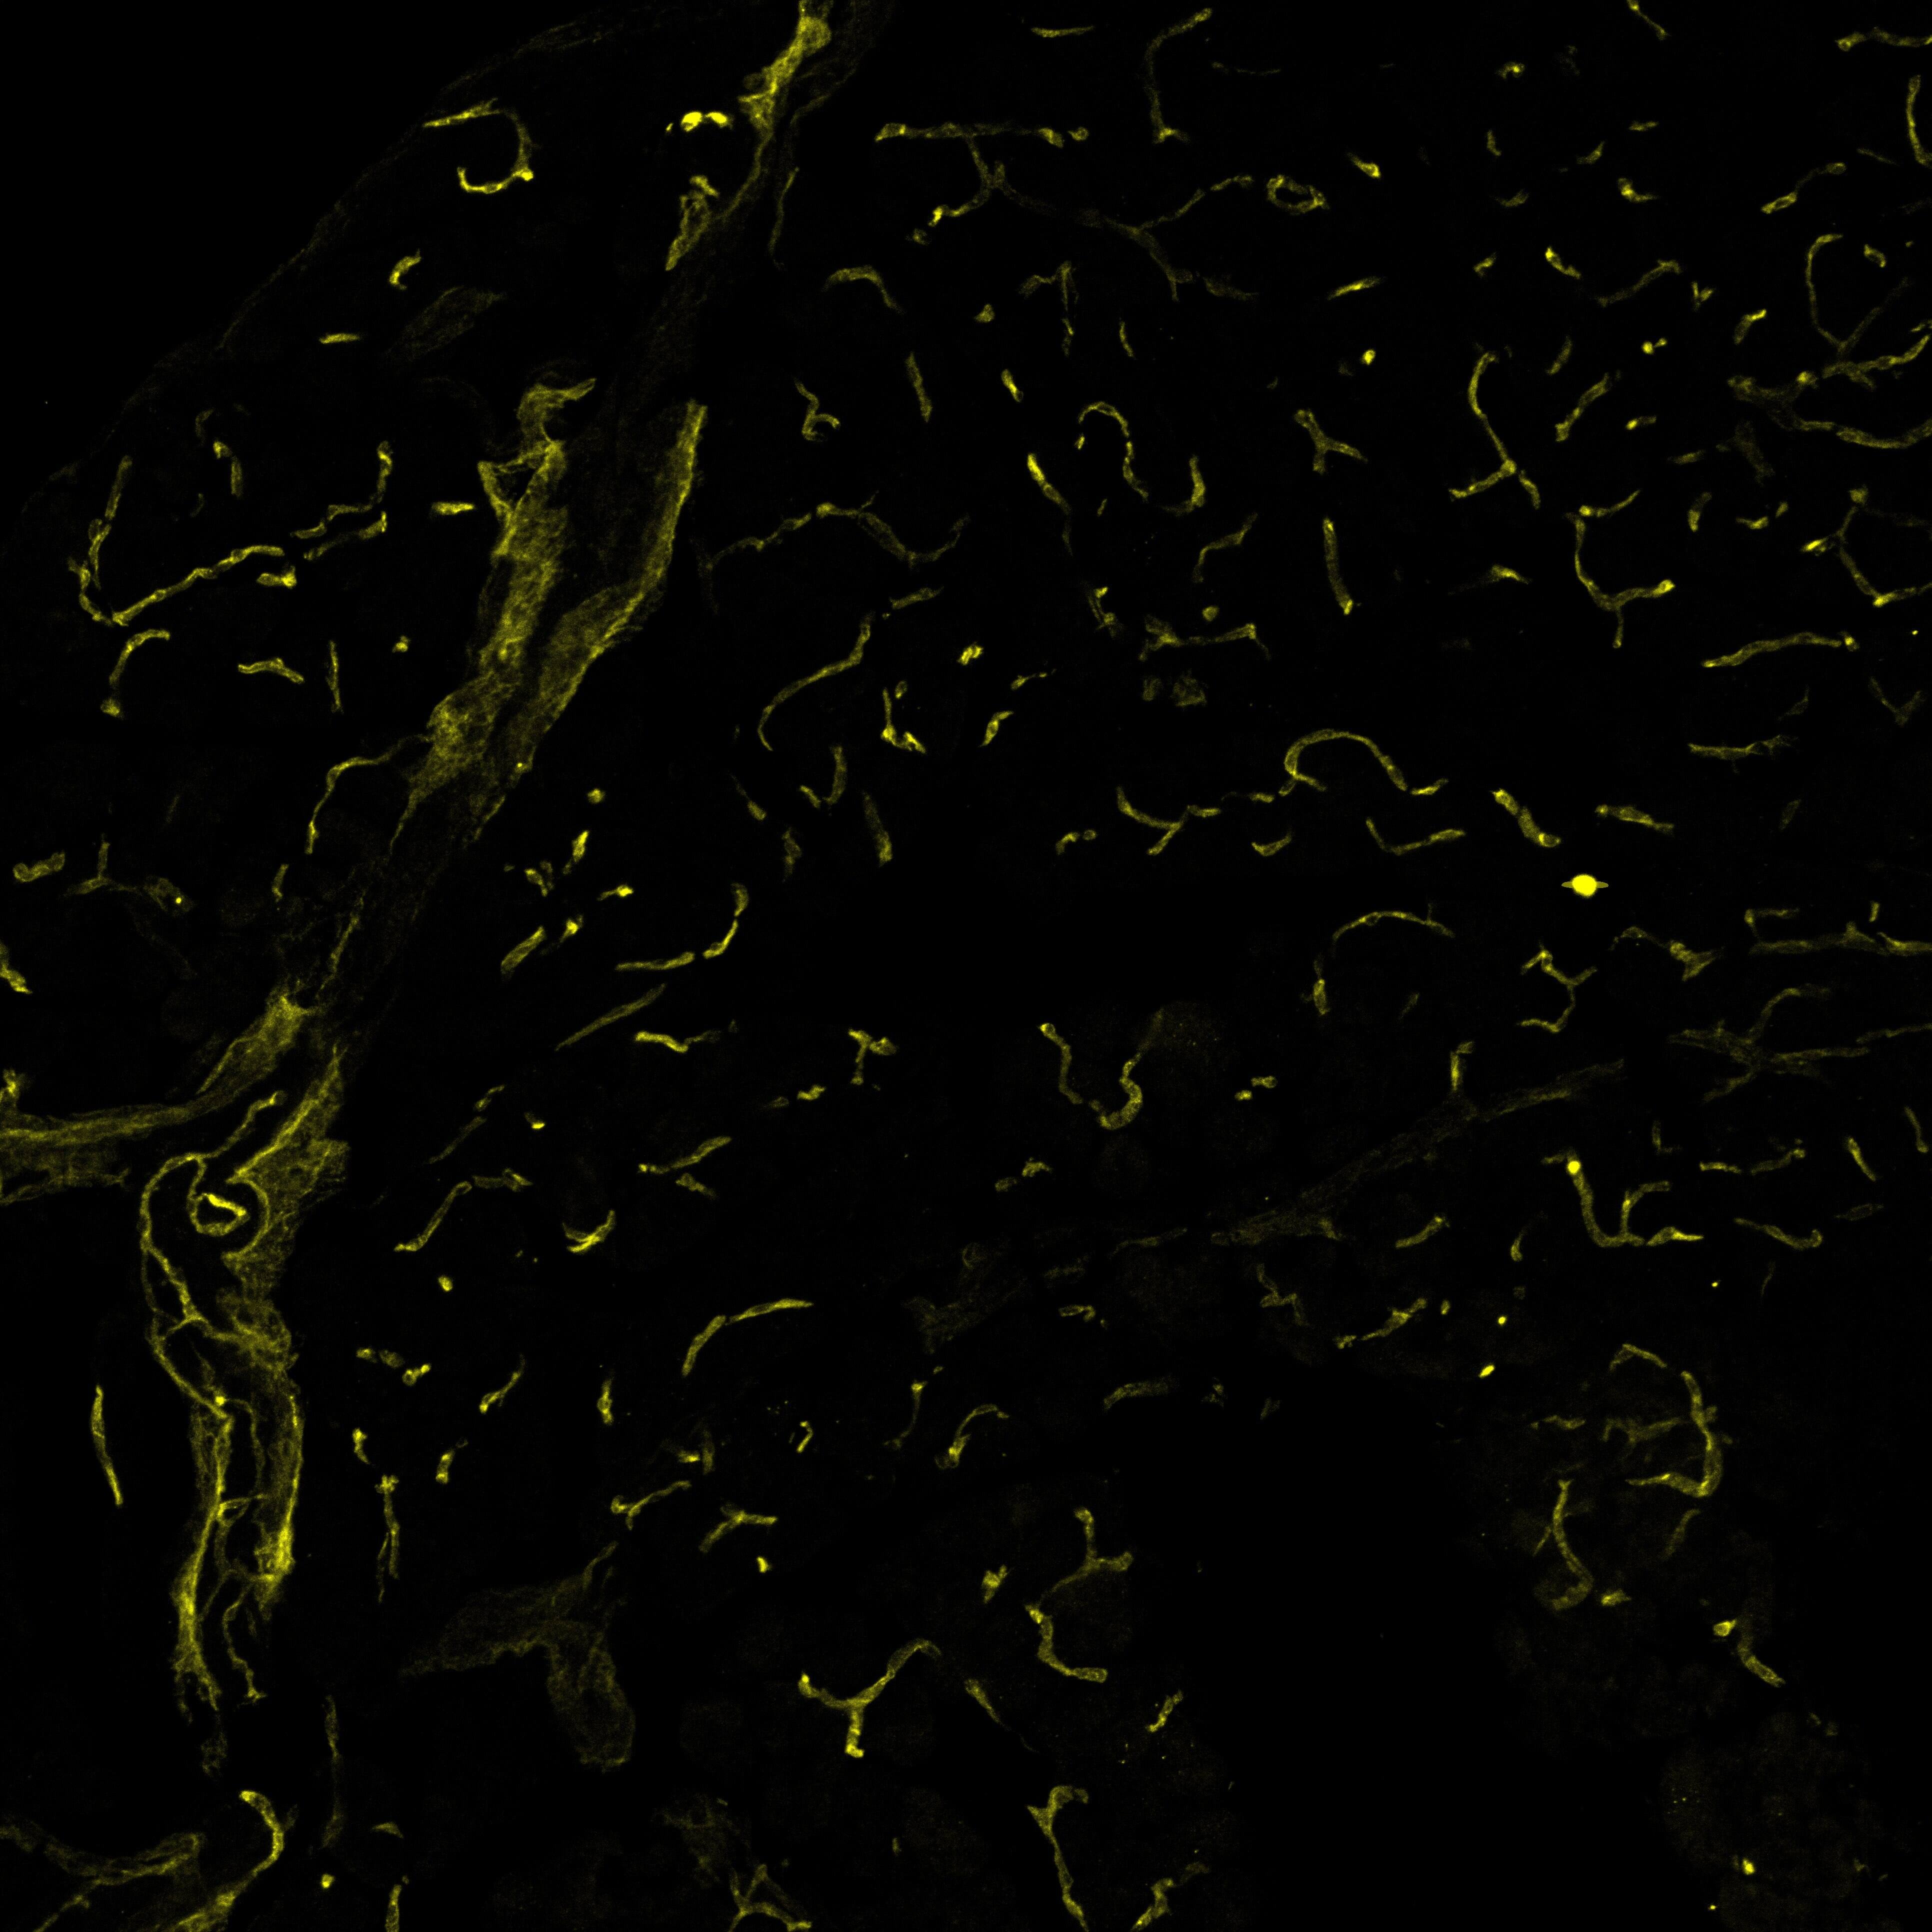

VEGFR2 antibody in Mouse Kidney Tissue.

VEGFR2 in Mouse Kidney Tissue.

VEGFR2 was detected in acetone fixed cryosections of mouse kidney tissue using Goat Anti-Mouse VEGFR2/KDR/Flk-1 Polyclonal Antibody (Catalog # AF644) for 50 minutes at room temperature. Tissues were stained with rabbit anti-goat secondary antibody and HRP polymer-conjugated anti-rabbit IgG followed by AEC+Substrate Chromogen (red) followed by counterstaining with hematoxylin (blue). Experiments were carried out and the image was provided by Dr. Grietje Molema, University Medical Center Groningen, The Netherlands.